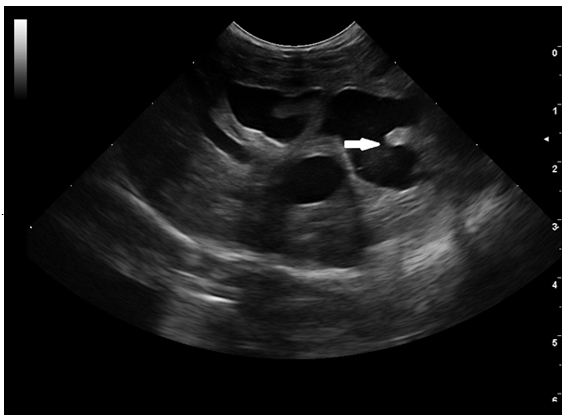

A standard blood test was performed, haematology and biochemistry revealed moderate leucocytosis [WBC-25.96 (2.87-17.02x10^9/L)], mild neutrophilia [12.15 (2.30 - 10.29 x10^9/L)], lymphocytosis [9.53 (0.92 - 6.88 x10^9/L)], monocytosis [1.05 (0.05 - 0.67 x10^9/L)] and anisocytosis, creatinine [17 (53 - 141 µmol/L)], increased ALP [445 (14 - 192 U/L, values for young patients)], elevated GGT [144 (0 - 1 U/L)], bilirubin-total [ 81 (0 - 15 µmol/L)] and lipase [1,214 (40 - 500 U/L)]. The rest of the results were unremarkable. An abdominal ultrasound was, findings revealed moderate hepatomegaly with homogeneous echogenicity. Generalized distended and tortuous ducts (between 5-7 mm) were noted within all liver parenchyma (Figure 1-red arrow), with the gallbladder being identified separately, with normal architecture. In this case, the abdominal distension was mostly caused by the dilated intrahepatic ducts, mimicking hepatomegaly. The common biliary duct was normal, followed up to the level of the duodenum, duodenal papilla was not well identified owing to the amount of ingesta. Mildly thickened biliary duct walls were seen at the level of the central liver. No obvious cause of biliary obstruction was identified. Color Doppler flow was used to confirm the absence of blood flow at the level of distended ducts. Due to the size and age of the patient (400 g and 2 months of age), symptomatic treatment was started with ursodeoxycholic acid10 mg/kg PO q24h, liver supplements based on SAMe (S-Adenosyl-L-Methionine), Silybin, Turmeric extract (Curcumin) and amoxicillin and clavulanic acid, 15 mg/kg PO q12h. Abdominal distension improved after 5 days, but treatment was discontinued after 1 week.

Figure 1 Initial ultrasound examination.

Longitudinal (A) and transverse (B) image of the liver- Diffuse tubulo-saccular dilatation, mostly within the right liver, was noted, with secondary compression of the local hepatic veins and arteries, subsequently causing turbulent and high-velocity blood flow, assessed with PW Doppler. The GB was identified, but in a more lateral position, most likely due to compression and mass effect of the distended intrahepatic ducts.

On abdominal ultrasound, the liver was enlarged and distorted by numerous coalescing anechoic structures. In the absence of a Color flow Doppler signal and localization of the hepatic blood vessels, the structures were presumed to represent intrahepatic biliary ducts.

A follow-up ultrasound performed 4 weeks after the initial examination, revealed an increase in the distention of the intrahepatic bile ducts (> 7 mm) (Figure 2A-white arrow) with echogenic material formation within the ducts (Figure 2B-red arrow), thickening of the gallbladder wall (1.4 mm)10,27 and multilayer pattern (double rim aspect).